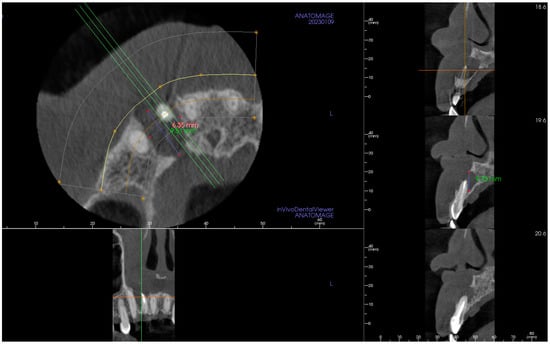

2. The Case